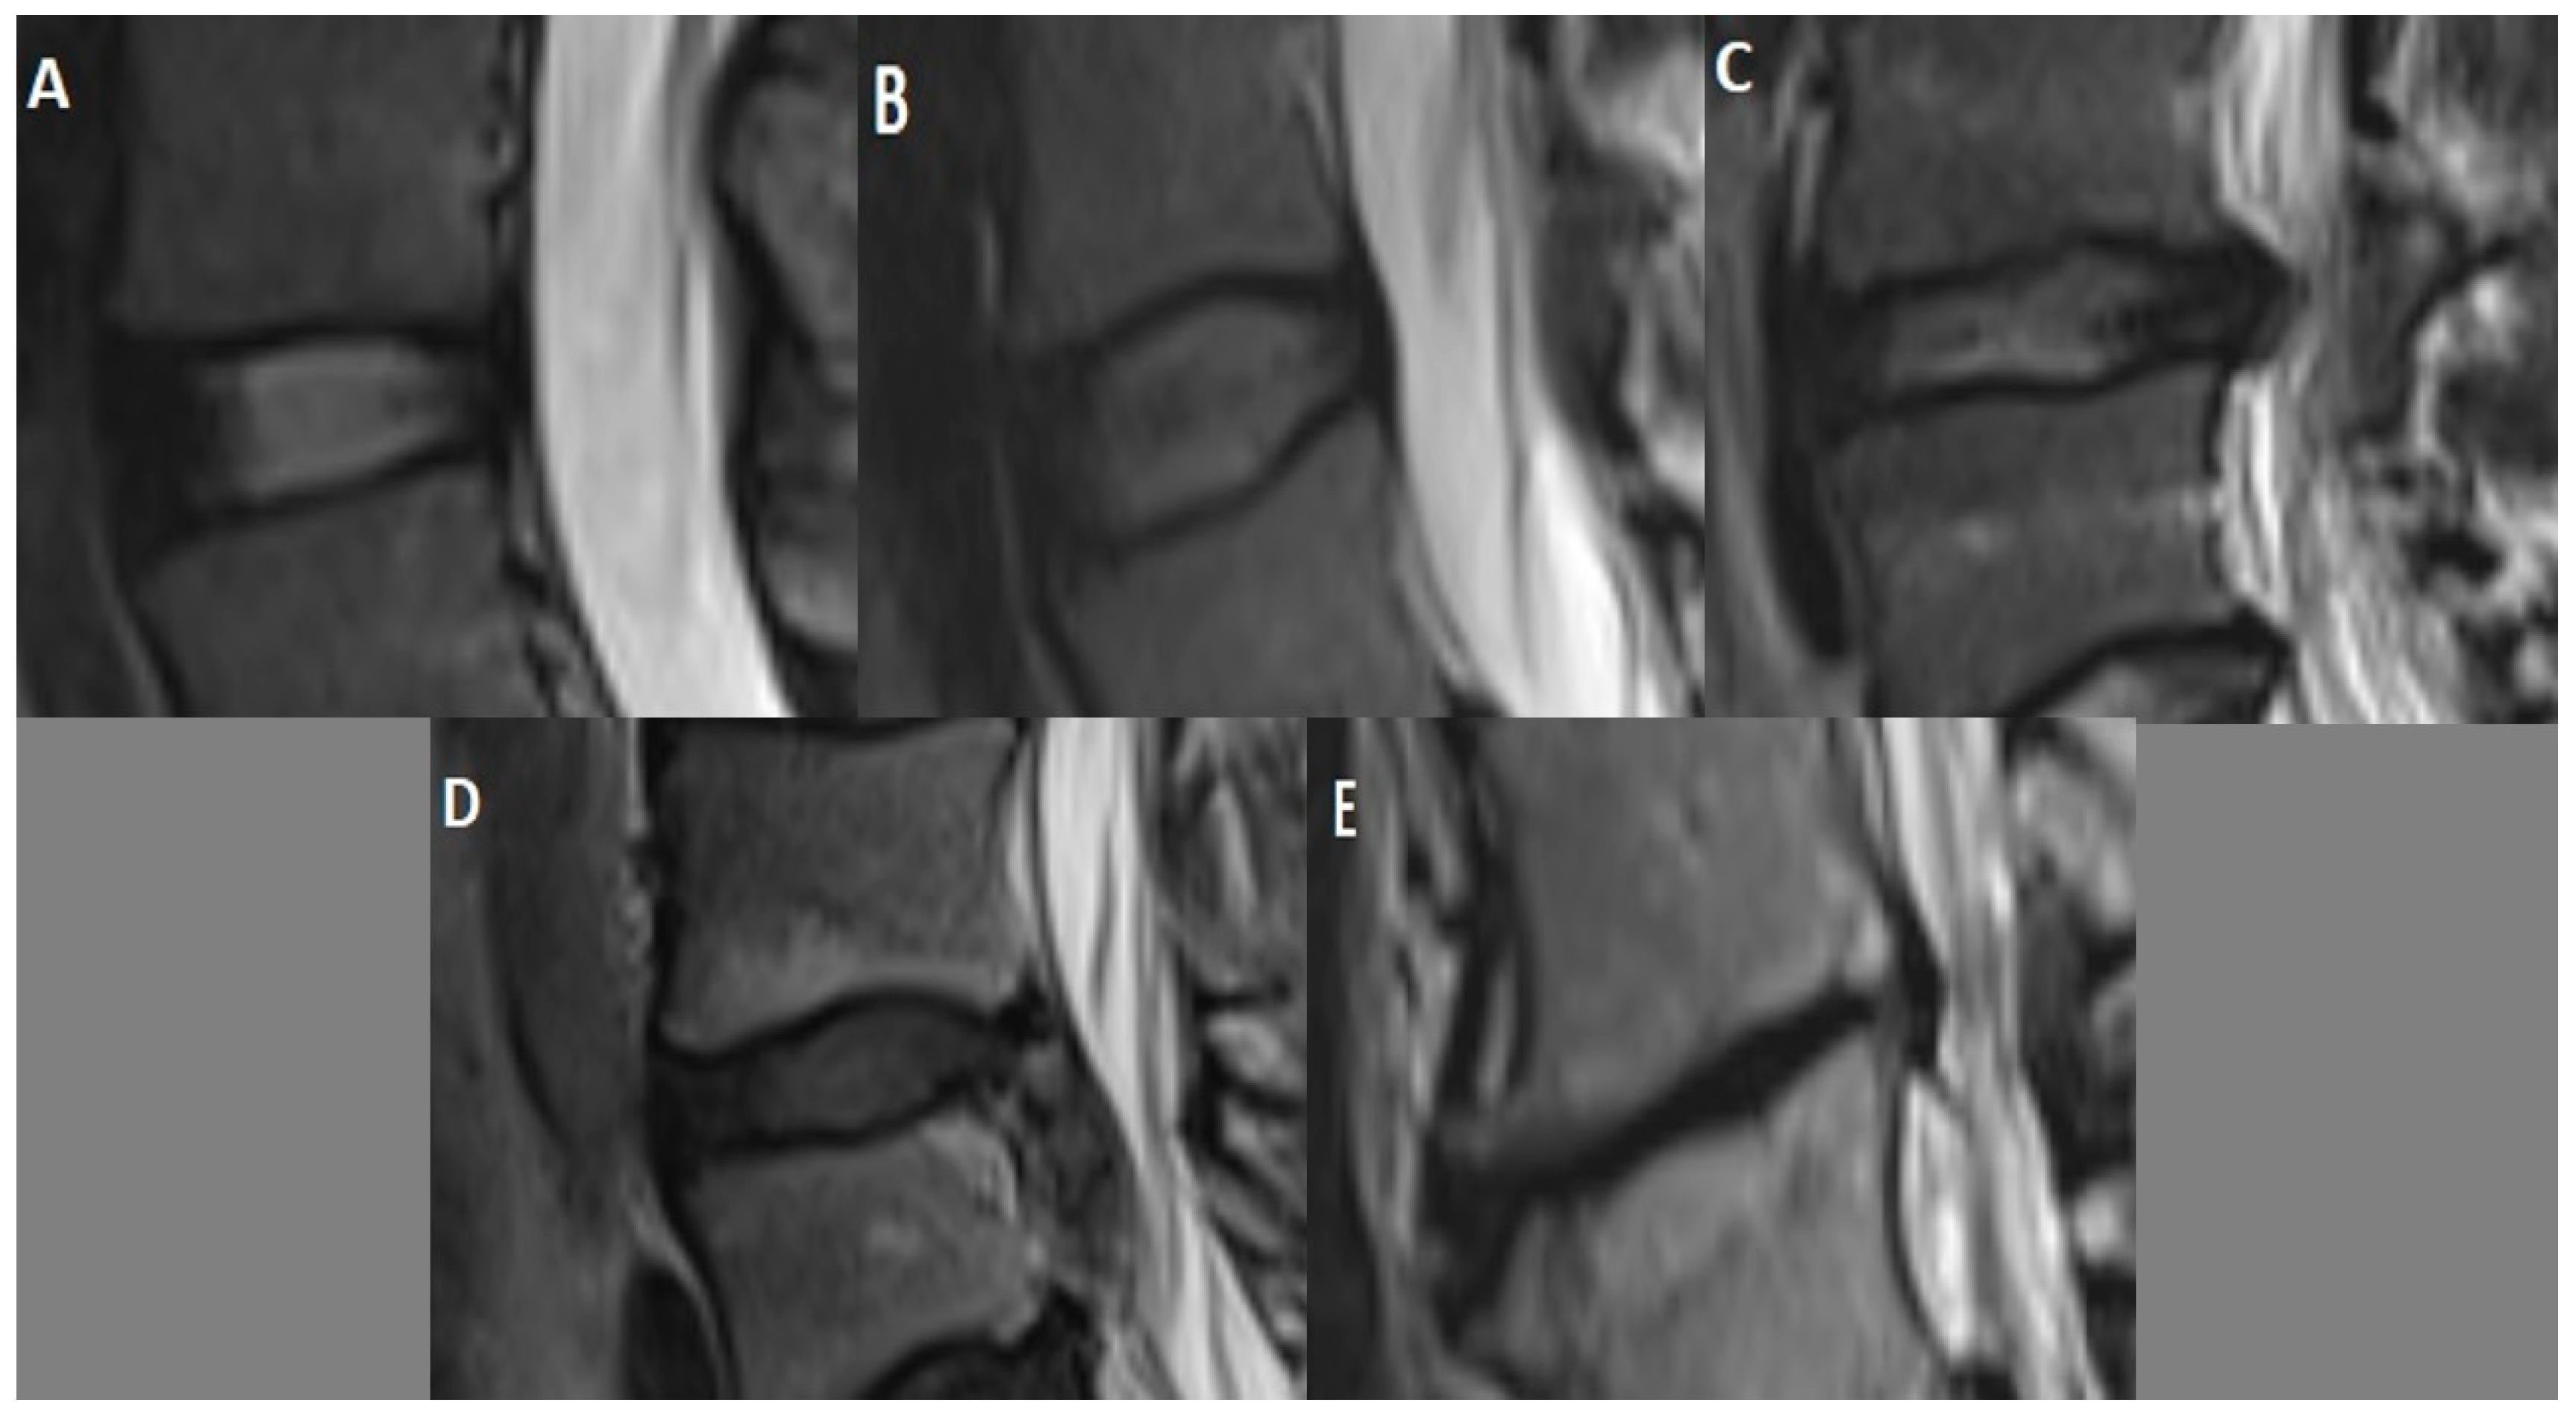

Figure 2.

Pfirrmann grading scale for intervertebral disc degeneration with sagittal T2-weighted MRI sequence: Grade I (A)—homogeneous white normal disc; Grade II (B)—inhomogeneous white disc, normal disc height, may have horizontal bands; Grade III (C)—inhomogeneous gray disc, slightly reduced disc height; Grade IV (D)—inhomogeneous black disc with no clear distinction between the annulus and nucleus, marked loss of height in the disc; Grade V (E)—inhomogeneous black collapsed disc.